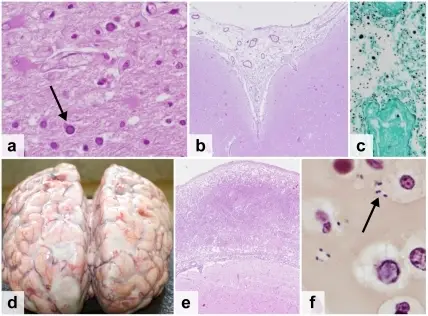

Bacterial Meningitis

- Increased neutrophils

- Decreased glucose

The causative organism may be identified by gram stain, polymerase chain reaction (PCR), Matrix Assisted Laser Desorption/Ionization – Time of Flight (MALDI-TOF), and culture.

The majority of the time, bacterial meningitis has complications.

Fungal Meningitis

- Increased lymphocytes

- Increased glucose